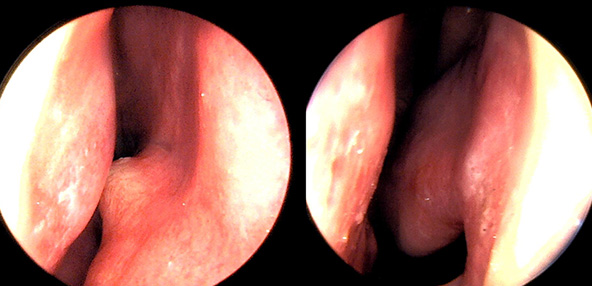

※ 비중격 비염 수술 후 생길 수 있는 부작용으로는 출혈, 감염, 염증이 있을 수 있습니다.

본 사진은 의료기관에서 진료를 본 환자이고, 전후 사진 인물이 동일인이며,동일조건에서 촬영이 되었습니다.